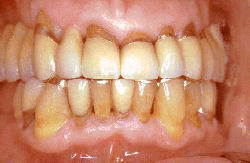

Varón de  63 años de edad con  enfermedad periodontal severa. Los dientes se han desgatado severamente y al sondaje de las bolsas periodontales encontramos una profundidad de  6-8 mm. En el canino inferiór puede observarse un épulis. Las señales de inflamación severa están presentes. La condición necesita tratamiento quirúrgico  con  gingivectomía, raspaje y alisado radicular. El paciente es instruído en los procedimientos de higiene oral.